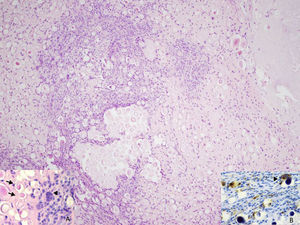

Abundantes cuerpos de psamoma, y proliferación de células mononucleares de hábito fusocelular (H&E ×100). A) Presencia de calcificaciones esféricas (flechas) y células gigantes multinucleares (cabeza de flecha) (H&E ×200). B) La inmunotinción con CD68 revela la presencia de células mononucleares dispersas, y rodeando las calcificaciones y células gigantes multinucleadas (cabeza de flecha) (CD68×200).

El diagnóstico fue de tenosinovitis con calcificación psamomatosa (TCCP). Aunque puede considerarse como una parte del espectro de las lesiones tumorales con calcificación, sus características clínicas e histológicas permiten considerarla como una entidad independiente, infrecuentemente reconocida, y rara vez comunicada en la literatura médica1–4. Clínicamente se presenta como un nódulo o masa subcutánea única, localizada principalmente en las zonas acras de las extremidades, de predominio en mujeres de edad adulta. Los pacientes refieren historia de traumas repetitivos de índole ocupacional, o relacionados con la realización de deportes2. Las lesiones se localizan en el tendón o en los tejidos blandos peritendinosos, y desde el punto de vista histológico se presenta como una proliferación compuesta por histiocitos y (mio) fibroblastos, y la presencia de numerosos cuerpos esferoidales psammoma-like.